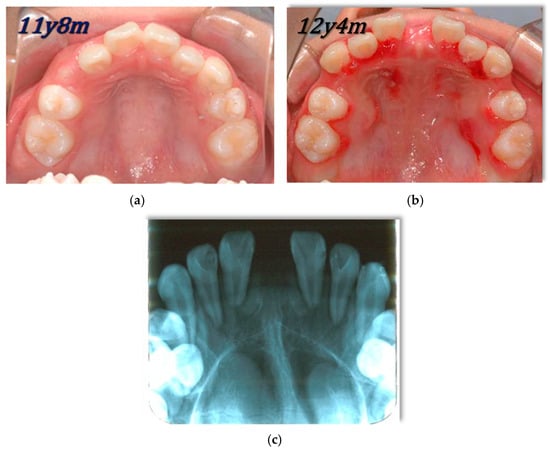

CBCT Volumetric Changes in Combined Nasal Cavity and Paranasal Sinuses Following RAMPA-ROA Therapy: A Retrospective Cohort Study with Reference to Longitudinal Growth Data

by

Yasushi Mitani, Yuko Okai-Kojima, Mohammad Moshfeghi, Tonogi Morio, Shouhei Ogisawa and Bumkyoo Choi

J. Clin. Med. 2026, 15(7), 2605; https://doi.org/10.3390/jcm15072605 (registering DOI) - 29 Mar 2026

Abstract

Background: The interrelationship between craniofacial morphology and respiratory function is a central focus of orthodontic and dentofacial orthopedic research. This study aimed to evaluate the volumetric changes in the sinonasal complex (combined nasal cavity and paranasal sinuses) following Right Angle Maxillary Protraction Appliance

[...] Read more.

Background: The interrelationship between craniofacial morphology and respiratory function is a central focus of orthodontic and dentofacial orthopedic research. This study aimed to evaluate the volumetric changes in the sinonasal complex (combined nasal cavity and paranasal sinuses) following Right Angle Maxillary Protraction Appliance (RAMPA) therapy using cone-beam computed tomography (CBCT) and to compare these outcomes with established longitudinal growth benchmarks. Methods: A retrospective cohort analysis was conducted on 60 pediatric patients (24 males, 36 females; mean age: 86.60 ± 24.22 months) with radiologically clear paranasal sinuses at baseline (T1). Participants underwent RAMPA therapy for an average of 8.38 months. Volumetric quantification of the entire sinonasal complex—including the nasal cavity and all four paranasal sinuses (maxillary, ethmoid, sphenoid, and frontal)—was performed to ensure methodological alignment with existing normative growth data. Results: Total sinonasal volume increased significantly from 27,741.63 ± 10,675.85 mm3 at T1 to 32,248.00 ± 10,084.07 mm3 at T2 (p < 0.001), representing a mean gain of 4506.37 mm3 (16.24%). Notably, the annualized growth velocity under RAMPA therapy (6453 mm3/year) exceeded the physiological increment of age-matched normative data (~5418 mm3/year) by approximately 1.2 times. Despite a constricted baseline at T1 compared to normative values, the treatment group demonstrated a rapid “catch-up” growth trajectory. Conclusions: RAMPA therapy induces rapid and significant volumetric expansion of the sinonasal complex in pediatric patients, demonstrating a potent “acceleration effect” that surpasses natural physiological maturation. These findings suggest that orthopedic midfacial remodeling can effectively restructure the upper respiratory environment, bridging the gap between pathological constriction and normative developmental benchmarks in patients with maxillary hypoplasia.

Full article

(This article belongs to the Special Issue Maxillomandibular Growth, Reconstruction and Rehabilitation: Orthodontic, Prosthodontic and Surgical Interventions from Childhood to Adulthood)